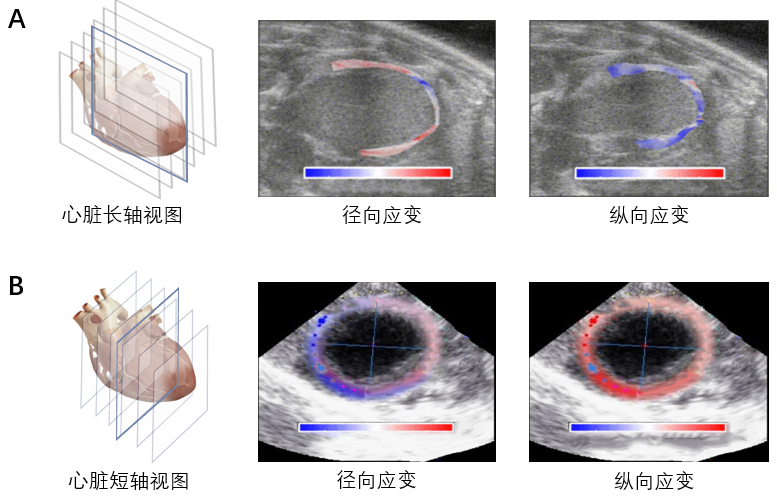

RTE测量方法。实验动物均常规建立静脉通道,麻醉状态下且给予心电监护。肌形变显像在客观评价心室功能的基础上,对获得有临床价值的信息具有重要作用。实时超声弹性成像技术(RTE)是一种利用超声射频数据提取心肌局部变形场的心肌变形成像方法。RTE利用心肌的自然收缩和松弛作为应变估计的机械刺激。如图6所示,A心肌的径向和纵向应变可视化结果,B心肌的轴向应变可视化结果。

图6 A心肌的径向和纵向应变可视化结果,B心肌的轴向应变可视化结果